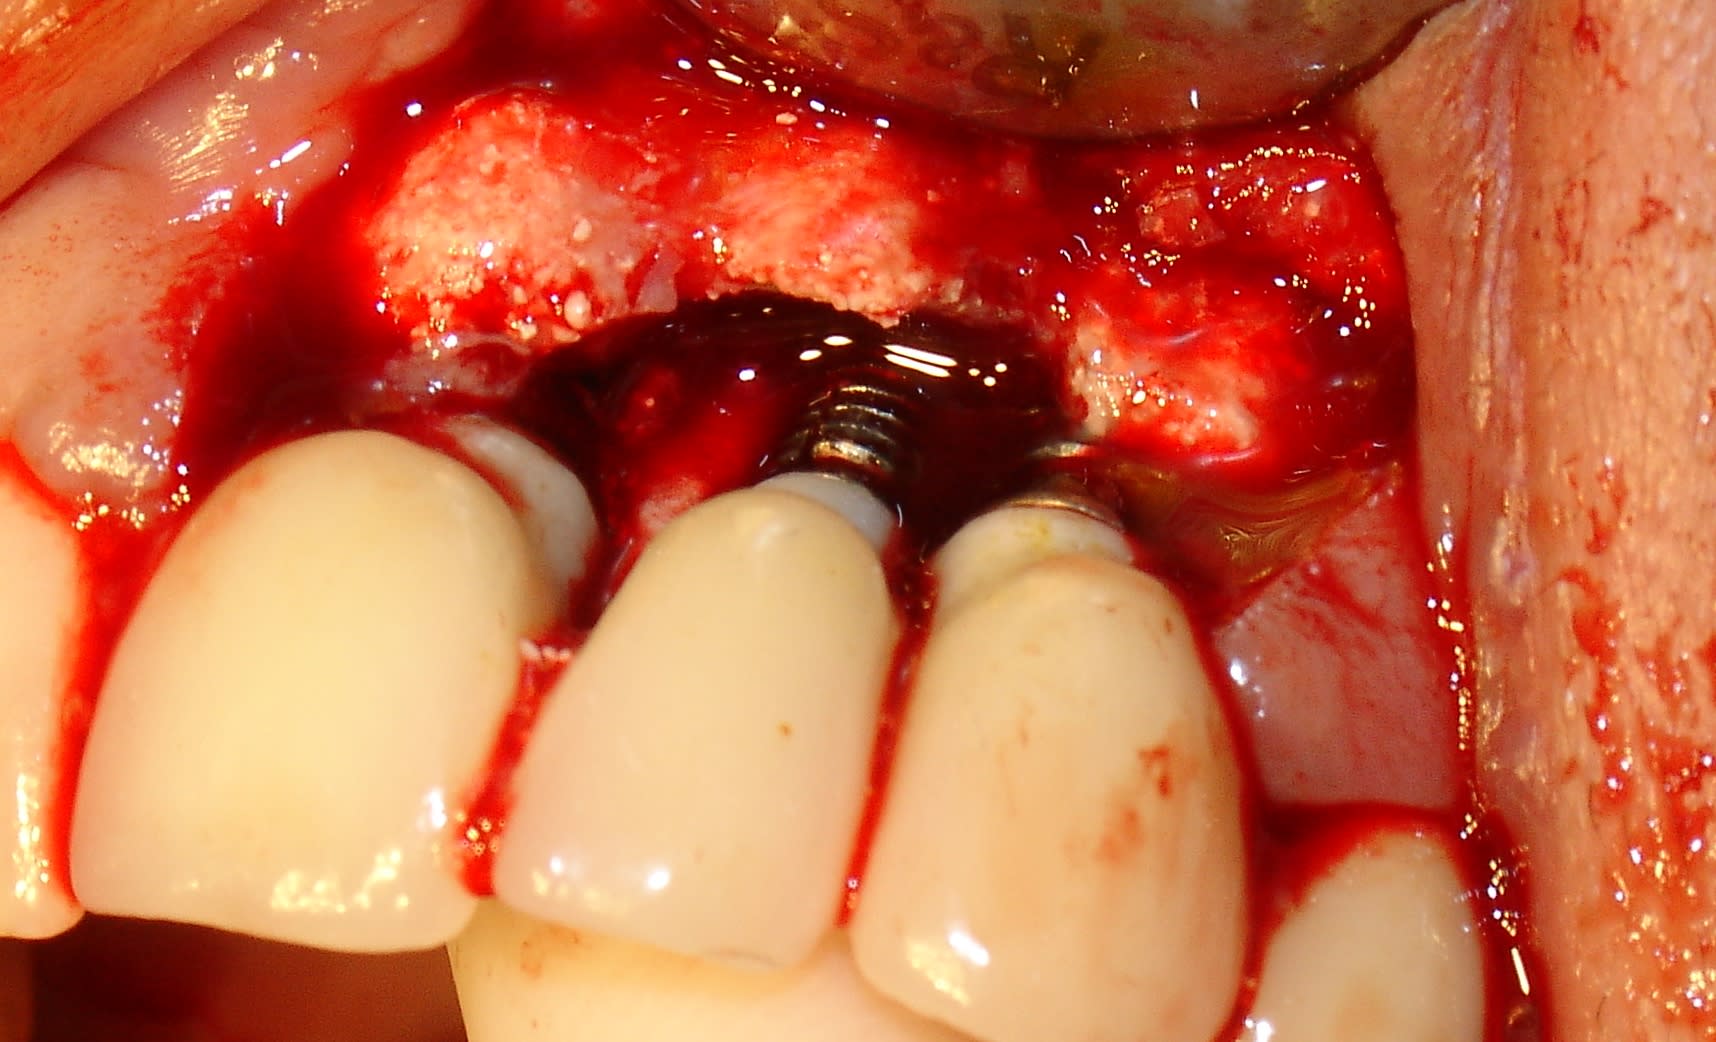

Je dirais pour le prix plus près de 300€, enfin très très cher car ils veulent se positionner en premium. Je sais j'y ai cru jusqu'à ce que les fractures arrivent.....fracture d'implant!

J'ai cru à une péri implantite quelle surprise ! Merci Megagen.....et quand je leur en ai parlé évidemment je suis le seul!....MDR Si je rajoute le SAV purée je suis largement perdant.

Voici un cas de molaire (le 1er) . Cela prouve que la taille de l'implant n'est pas la cause.

L'autre cas est une 22 (peri implantite mais NON).